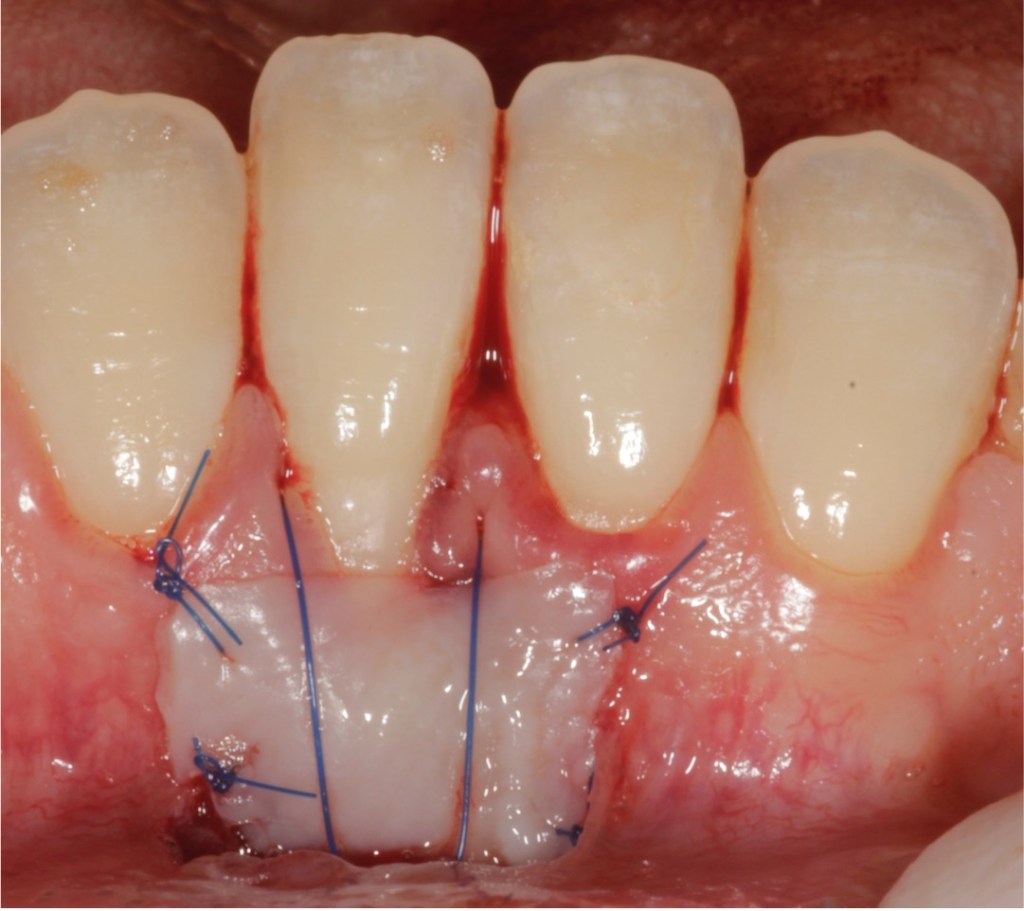

Recession surgery – Free gingival graft

A free gingival graft can cover the recession area and provide “tougher” gum to prevent further recession and make brushing more comfortable. This can also be done around implants. The graft is taken from the roof of the mouth which heals over after a few weeks.